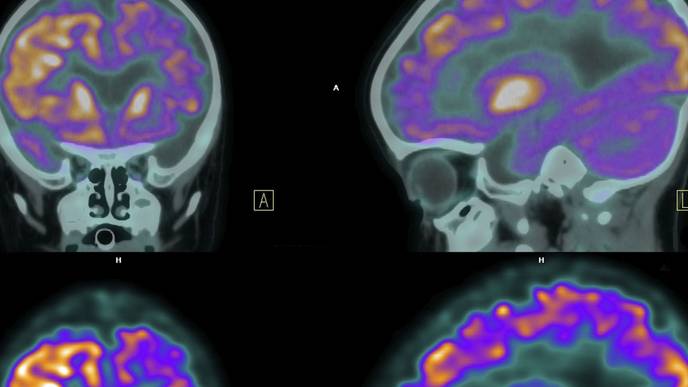

A recent case report highlights a complete and sustained response to immunotherapy in a patient with stage IV non-small cell lung cancer (NSCLC) and brain metastasis. Published in Oncoscience, the report documents a 51-year-old male patient who experienced durable survival and maintained quality of life after treatment with whole-brain radiotherapy (WBRT) followed by an immune checkpoint inhibitor (ICI).

This case illustrates the evolving potential of immunotherapy in patients with advanced NSCLC, particularly those with brain metastases, a group typically facing poorer outcomes. Following WBRT, the patient achieved both intracranial and extracranial responses, with no disease progression for over six years. His overall survival currently stands at 87 months, and progression-free survival at 73 months, providing a significant example of extended remission in the context of metastatic NSCLC.